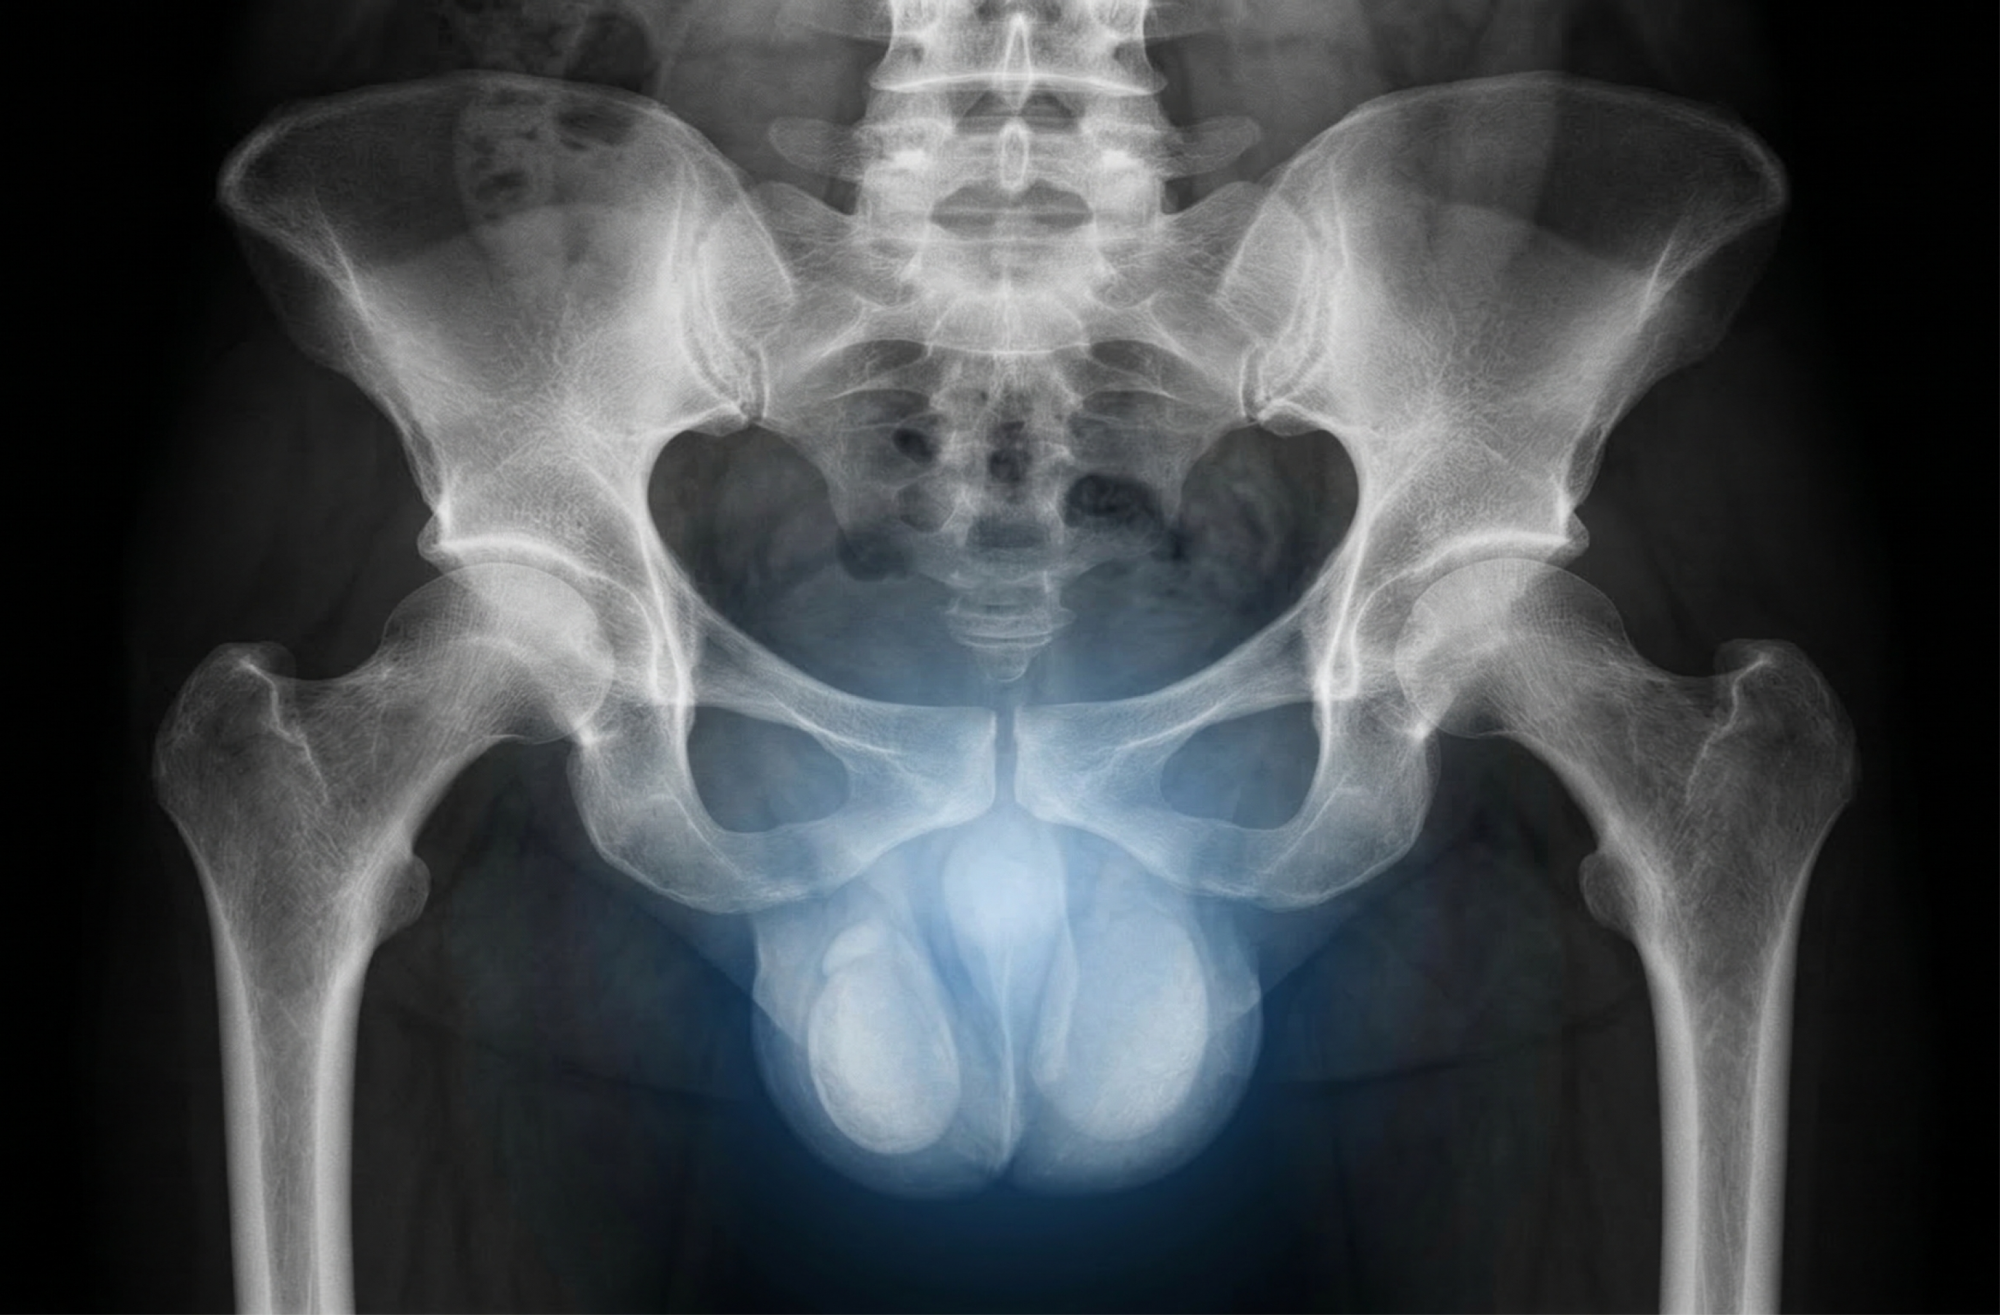

УЗИ мошонки у мальчиков: о чем молчат подростки и что должны знать мамы

Ультразвуковое исследование яичек (диагностика варикоцеле) на аппарате экспертного класса.

Здоровье будущего мужчины закладывается в раннем детстве, но тема мужской половой сферы часто остается «неудобной». Мальчики стесняются жаловаться на дискомфорт, а мамы боятся задать лишний вопрос. Рассказываем, зачем делают УЗИ органов мошонки, как вовремя распознать варикоцеле у подростков и почему при перекруте яичка счет идет на часы.

Период активного роста (12–15 лет) — время, когда у мальчиков может развиться варикоцеле (расширение вен семенного канатика). Коварство этого состояния в том, что оно редко болит. Ребенок может чувствовать лишь легкую тяжесть после физкультуры, которой не придаст значения.

Почему это важно? Расширенные вены повышают температуру внутри мошонки, что губительно для клеток, отвечающих за детородную функцию. УЗИ с допплерографией позволяет выявить варикоцеле на самых ранних стадиях, когда проблему можно решить бережно, сохранив мужское здоровье на всю жизнь.

Перекрут яичка: когда счет идет на часы

Это критическое состояние, о котором должен знать каждый родитель мальчика. При перекруте яичко поворачивается вокруг своей оси, перекрывая кровоток.